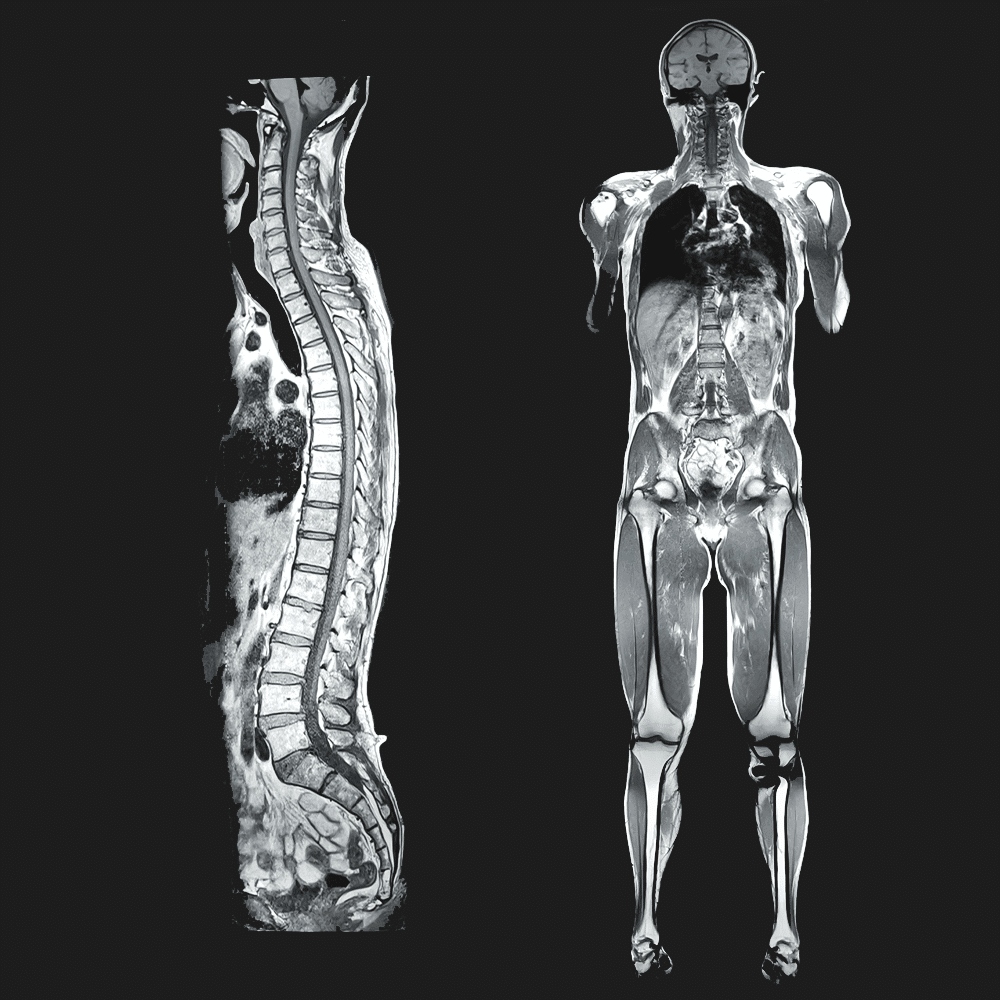

Our Male Screening Package is a comprehensive preventative health bundle designed specifically for men. It combines a Whole Body MRI, Prostate MRI Screening, & Coronary (Cardiac) CT Angiography to assess key areas of men’s health using advanced non-invasive imaging. This is a private, self-pay package and is not covered by OHIP.

Whole Body MRI

Screens major organs and structures from head to knees in one exam